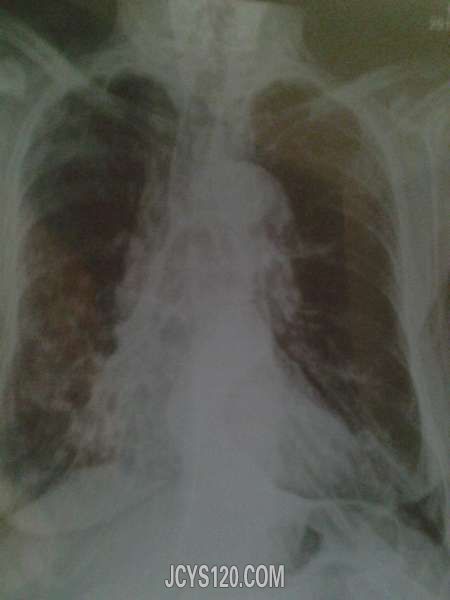

患者7天前因受凉后感到恶寒,无发热,继之咳嗽,阵发性,白色泡沫性痰液,伴胸闷明显,无胸痛,盗汗,乏力,家里有消炎药和止咳药吃了几顿,病情没有减轻,反而加重,痰中有血丝,于是在家人的护送下来到县医院拍片示为右下肺多发性肺囊肿伴慢性感染和心脏扩大,要求住院治疗,患者拒绝带药回家,GS500ml+阿奇霉素0.5vgtt,qd.×三天,阿莫西林分散片0.5tid,必漱平16mgtid.第四天效果不显。

神清,精神差,慢性病面容,查体合作,步入卫生室,全身无淋巴结肿大,头颅大小正常,双眼睑无水肿,无充血,瞳孔等大等圆,对光反射敏感,鼻中隔居中,口唇稍紫绀,牙齿部分脱落,颈部对称,无颈静脉怒张,气管居中,胸廓对称,肋间隙稍微增宽,呼吸音有痰鸣音,湿性罗音,语颤减弱,心音低沉,心脏向左侧扩大,听诊无杂音。腹部正常,下肢无水肿。

患者要与肺结核,支气管扩张,肺癌,心衰等鉴别。